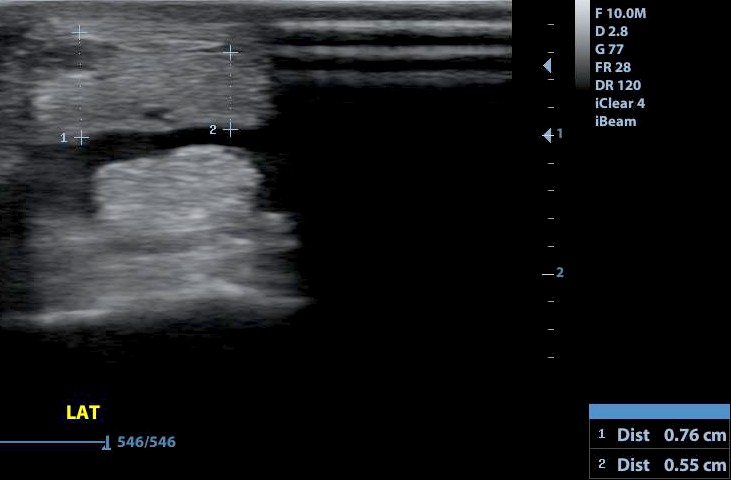

A mély ujjhajlító ín csüd alatti sérülése bejelölve. A mérés alapján a keresztmetszet 11 százalékát érintő sérülés.